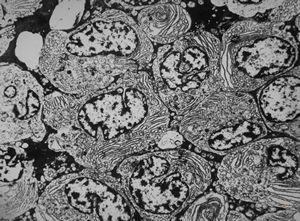

M,62y. | bone marrow - plasmocytoma

M,64y. | bone marrow - plasmocytoma

bone marrow … plasmocytoma (parafin-embedded sample)